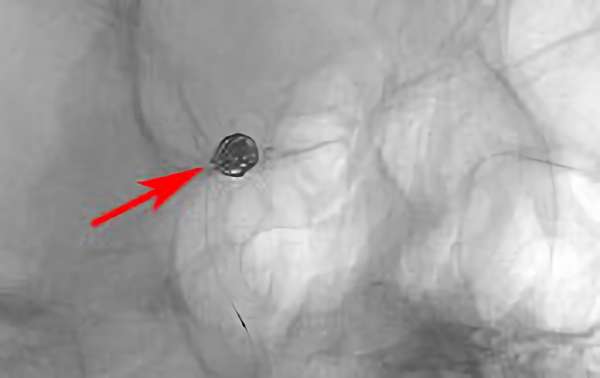

No.1628 手術前